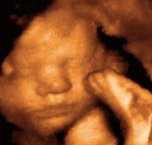

A rohamos növekedés lassulni kezd, ám az agy fejlődése lényegesen felgyorsul. Ekkorra az egyetlen létfontosságú szerv, amelynek még érésre van szüksége, a tüdő. A kiválasztás már teljes gőzzel működik: a magzat naponta mintegy fél liter vizeletet ürít a magzatvízbe. A fejlődéséhez szükséges tápanyagokat a lepényi keringésen keresztül kapja meg, de már elkezdte nyeldekelni a magzatvizet, amely természetesen folyamatosan pótlódik és cserélődik. Az ultrahangos vizsgálat alkalmával a kezelőorvos ellenőrzi a magzatvíz mennyiségét. Ha túl sok van belőle - ezt polihidramnionnak hívják -, a magzat nem nyel eleget, vagy valahol elzáródás található a gyomor-bélrendszerében. Ha túl kevés a magzatvíz mennyisége - ez az oligohidramnion -, a kicsi nem ürít megfelelően, ami a vesék és a húgyutak rendellenességét jelentheti.